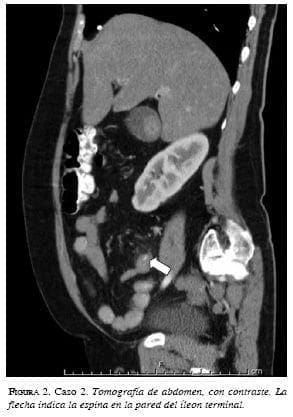

Una mujer de 65 años consultó por dolor abdominal difuso de tipo cólico de cuatro días de evolución, fiebre no cuantificada, sin vómito y hábito intestinal normal. Tenía antecedente de evento cerebrovascular 10 años atrás sin secuelas e histerectomía abdominal por miomatosis. En el examen de ingreso se registró taquicardia, taquipnea, y leucocitosis, y dolor en flanco y fosa ilíaca izquierda. Se practicó TC de abdomen, con contraste, ante la sospecha de enfermedad diverticular complicada, que evidenció perforación del íleon distal por una estructura hiperdensa de 28 mm, asociada con alteración de la grasa adyacente; además, se encontró ureterolitiasis derecha (figuras 2 y 3). Se llevó a cirugía, y se encontró perforación por espina de pescado en el borde antimesentérico, a 15 cm de la válvula ileocecal, con plastrón adyacente a la lesión y sin peritonitis. Se practicó hemicolectomía derecha con anastomosis lateroterminal de íleon a colon transverso con sutura mecánica. En el posoperatorio presentó dehiscencia de la anastomosis, que requirió ileostomía, con fístula mucosa y múltiples lavados abdominales, con una evolución muy tórpida en cuidado intensivo y con deterioro progresivo. Un mes después de su ingreso al hospital, la paciente falleció por falla respiratoria.

La Tomografía computadorizada (TC) se considera el método de imaginología de elección, porque permite identificar la presencia, el sitio y la causa de la perforación intestinal 19-22. Se puede ver extravasación del medio de contraste oral, engrosamiento de la pared intestinal y aire libre en la cavidad abdominal, como signos radiológicos directos que sugieren perforación intestinal 23-25. La infiltración grasa, el absceso o el flegmón adyacente al intestino, y la obstrucción intestinal asociada, son signos indirectos 6.